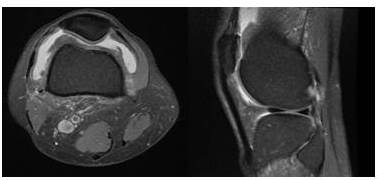

La mayoría de los pacientes refieren historias de dolor local crónico, aumento de volumen y limitación funcional articular no asociado a un evento traumático previo. El diagnóstico se establece con la clínica apoyado en los estudios de imágenes, especialmente en la resonancia magnética, los hallazgos típicos incluyen hidrartrosis, levantamiento de la cápsula articular, masa de tejidos blandos, pudiendo existir erosión ósea hipointensa en T1 y T2 debido a los depósitos de hemosiderina en el tejido afectado y realce de la membrana sinovial hiperplásica e hipervascular posterior a la administración de contraste y puede haber estructuras quísticas con centros hipointensos en T1 e hiperintensos en T2. El diagnóstico se puede confirmar mediante biopsia de la membrana sinovial vía artroscópica (1).

En cuanto a la técnica de RTE empleada, la más utilizada fue la radioterapia con planificación 2D en 51,5 % de los pacientes seguida de técnica conformada con planificación 3D (RTC3D) en 48,5 %. Para la planificación del tratamiento en los casos tratados con RTC3D, se realizó tomografía computarizada con protocolo de radioterapia, con uso de colchón inmovilizador, dichas imágenes obtenidas fueron fusionadas en el sistema de planificación con estudios de resonancia magnética nuclear, esto permitió mejorar la delimitación del volumen a tratar (Figura 1). Posteriormente se realizó el plan de tratamiento, tomando en cuenta la dosis de tolerancia de los tejidos normales y conformando la dosis de la manera más precisa a nivel del volumen blanco (Figura 2). La dosis total promedio fue de 4 400 cGy (rango 1 050 - 5 000 cGy). El tiempo promedio de tratamiento radiante fue de 28 días (rango 8-35).